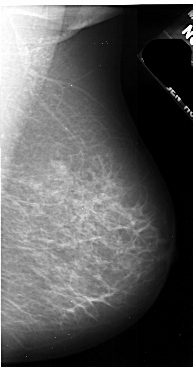

A_1036_1.RIGHT_MLO

RIGHT_MLO LINES 5491 PIXELS_PER_LINE 2881 BITS_PER_PIXEL 16 RESOLUTION 42 NON_OVERLAY